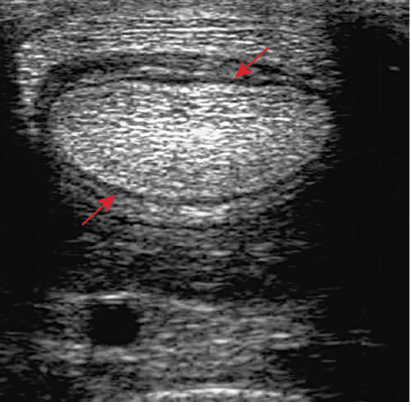

- The sheath is distended by anechoeic fluid. The arrows show the swollen synovial tissue, which is separating the DDFT from the SDFT and its manica flexoria.

- The sheath is distended by anechoeic fluid. Arrow showing the swollen vincula and the arrowheads show swollen synovium surrounding the tendons.